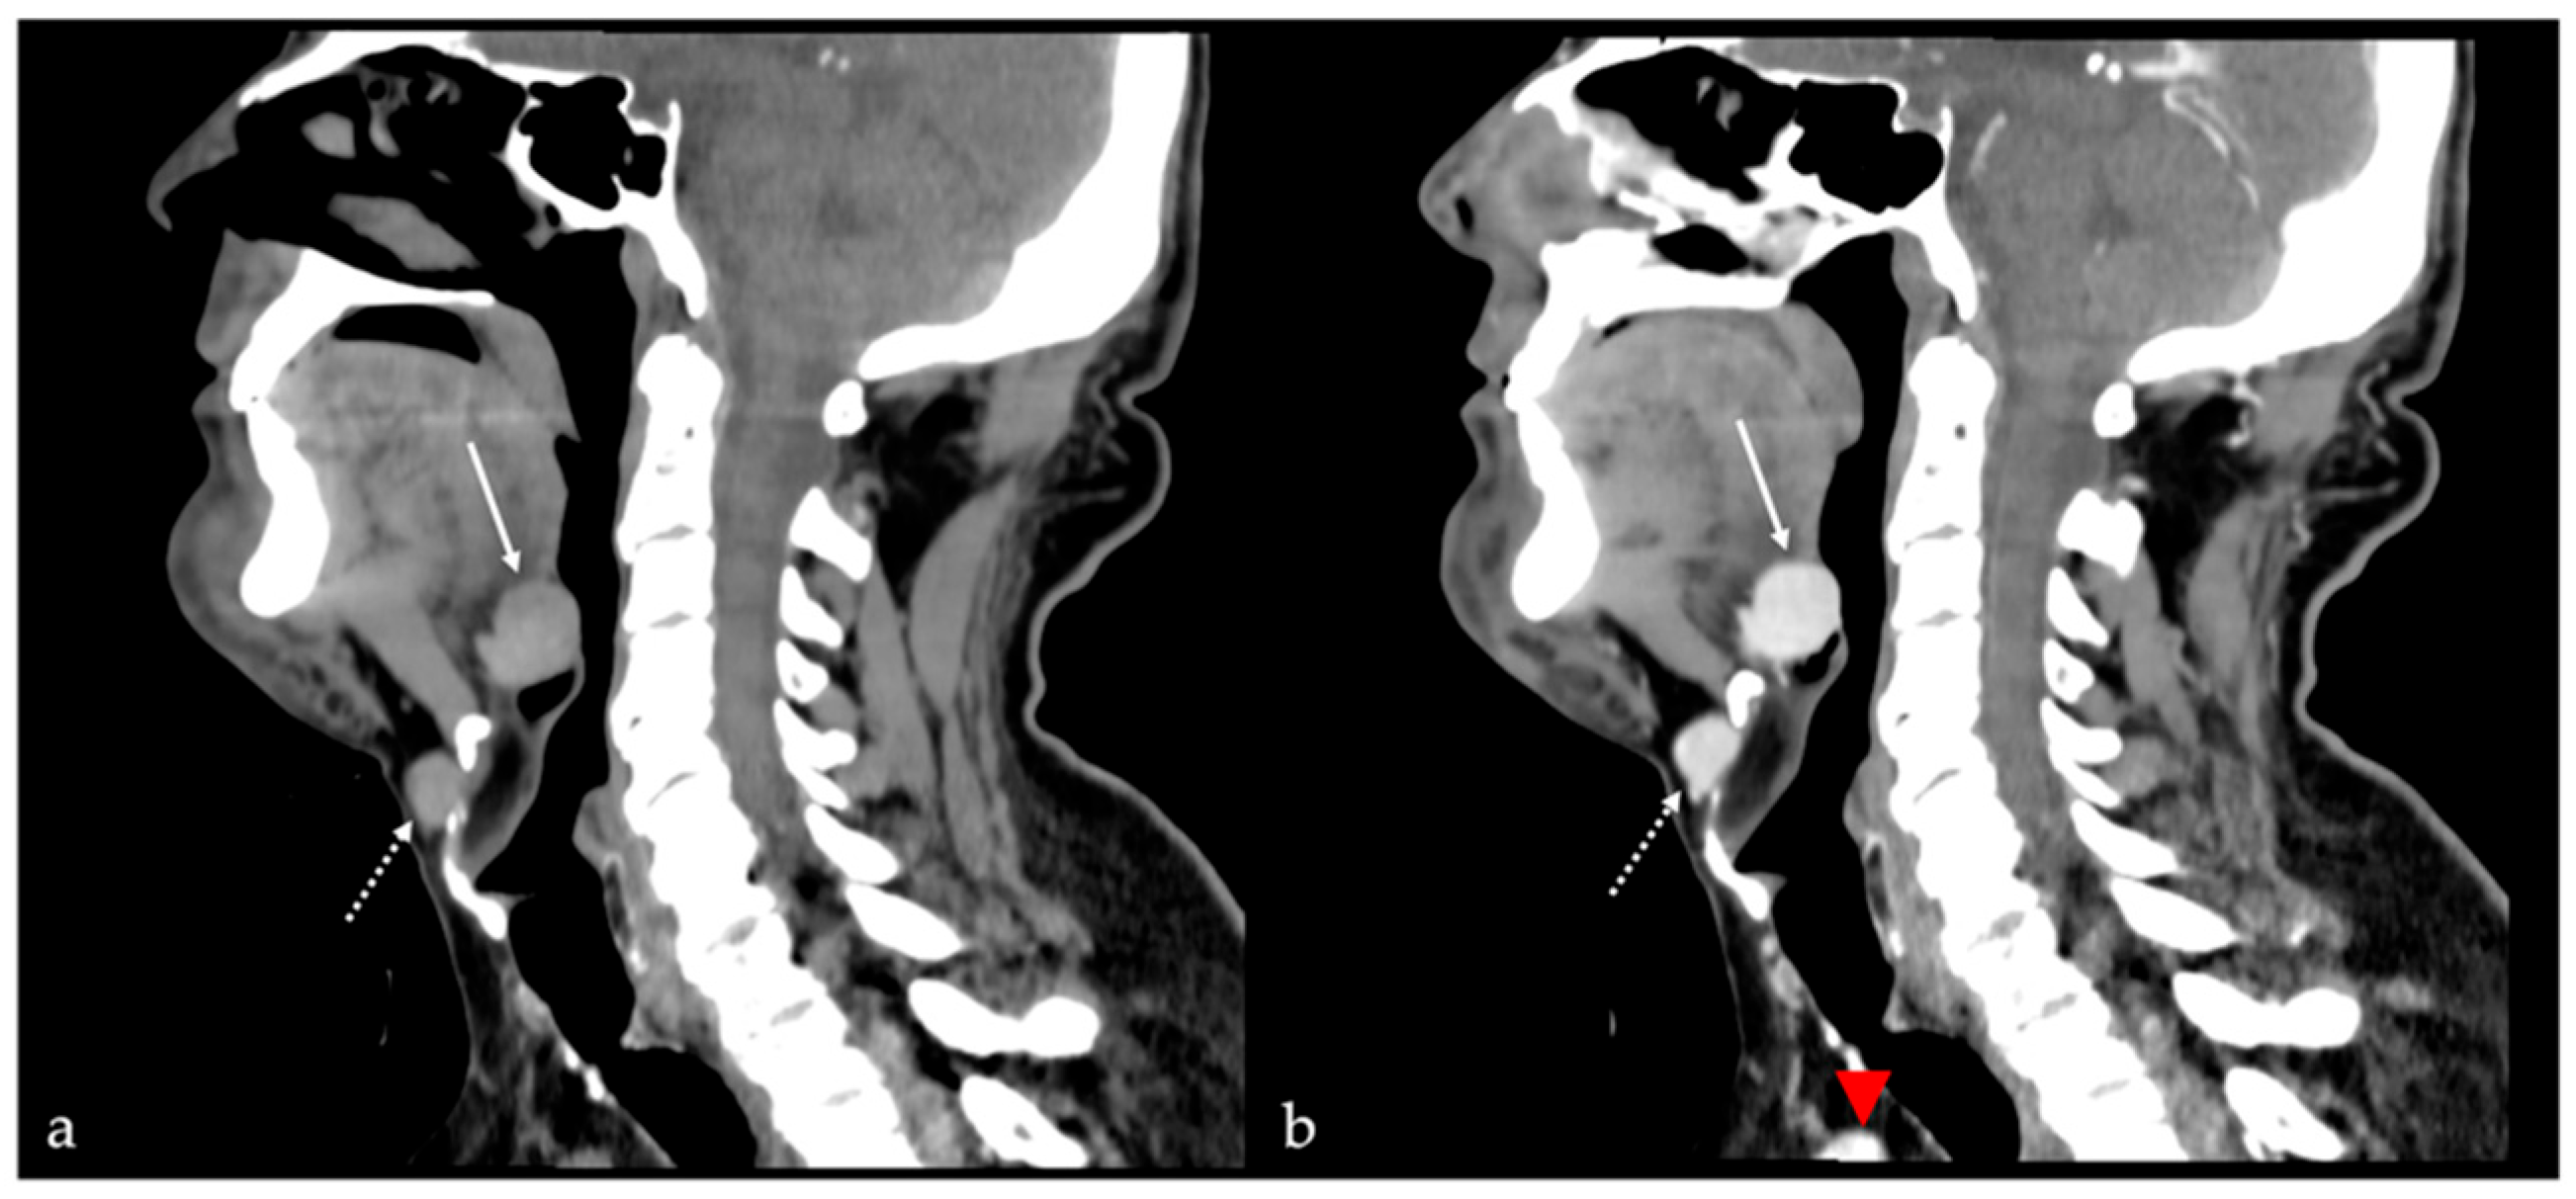

8. Lingual Abscess

9. Lingual Tonsillitis as Manifestation of Infectious Mononucleosis

| Abscess [17] | CT, MRI: peripheral enhancement MRI: core of the lesion shows high SI on DWI, and restricted diffusion with low values on ADC map | Submucosal malignancy |

| Lingual tonsillitis in infectious mononucleosis [18] | CT, MRI: symmetric tonsil enlargement, retention cysts, and “linear or columnar pattern” of enhancement (features of benign tonsillar hypertrophy) | Lingual tonsil lymphoma |